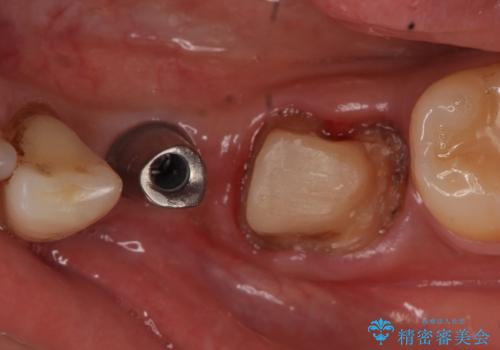

インプラント 左下奥歯の咬み合わせの改善

- 左下の歯並びが悪く、左側で物が咬みにくいので診て欲しいといらっしゃった方の症例です。

歯列矯正は御希望されなかったため左下4、5番目の歯を抜歯し、インプラントによる欠損補綴を行いました。

左下6も再根管治療後、オールセラミッククラウンによる補綴を行いました。